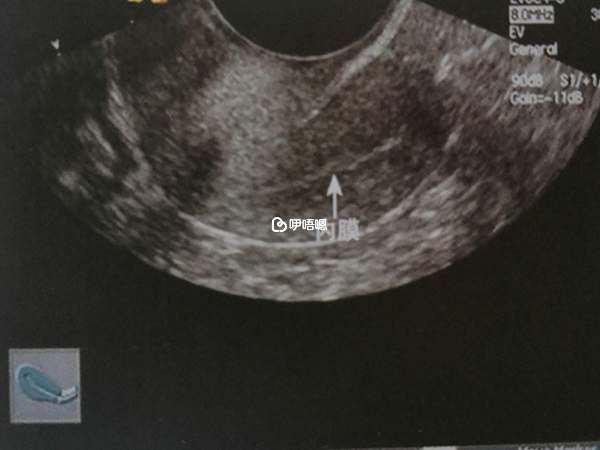

1.30,這兩次去都沒有掛到原來的大夫,都趕上她沒在,很鬱悶,別的大夫感覺不是一直給看的病人,都不是很認真,而且說話都讓人很挫傷信心。今天陰超顯示泡泡1.8*1.8了,心裡本來挺開心,開始以為這次泡泡頂多長到1.5,因為開始還沒開始陰超,大夫就拉著臉來一句,可能打針打不完就放假了啊。

後來陰超顯示泡泡長了。而且1.8了,我正開心呢。大夫來一句張力欠佳,給你打針排了吧。弄的我一頭霧水,大夫那口氣就好像這個泡泡不能要一樣的。弄的著心裡啊!趕緊追著大夫問,張力欠佳什麼意思。

2.22,今天上午去了醫院b超結果顯示泡泡1.0,內膜0.5.大夫說因為泡泡還不大所以內膜還是有點點薄,再等等,看看泡泡長不長呢,再過兩三天再去b超下。不過下次不想去市裡醫院了太遠了,在家附近的醫院b超下,等到1.7到1.8的時候再去找我的大夫。然後呢。嘿嘿。我就去逛街了,買了一身滑雪服,超級喜歡,然後下午又很幸運的定了晚上的滑雪票。吼吼~~晚上滑雪去嘍。

還好有一個1.4*1.2*1.0的泡泡,內膜0.7,不曉得算不算優勢呢,不過右側卵巢十個小卵泡,左側七八個,不曉得是不是我的多囊他又回來。因為這次不是在看病的醫院做的b超所以也說不出來什麼,只是知道泡泡確實是漲了,還是比較開心的。晚上繼續吃雪蛤。

3.25,今天月經第十一天了,排了好長時間的隊,做了血素四項,要下午四點才能取結果,順便做了b超。結果還真給我不小的打擊。內膜剛剛0.5,泡泡才0.8,大夫很嚴肅的告訴,沒有優勢,我崩潰,我鬱悶。

說下b超結果吧:子宮前衛,大小4.3*3.9*2.8,內膜0.5,子宮肌層回聲勻質,左卵巢:內可見3—4個卵泡,最大直徑0.8CM,右側卵泡:內見5-6個,最大直徑0.8。

去b超了,結果很領我吃驚,我本以為我的泡泡最多長到1.4左右,沒想已經1.6*1.5*1.5了,太讓我吃驚了,做b超的時候,大夫開始沒說話,我以為又沒戲了呢,大夫忽然說,是有個大泡泡,我賽。跟吃了蜜是的,不過內膜比較薄,但是還是很開心,這個月本來就是隨便啦,我的泡泡真的能自己長大。好開心哦。